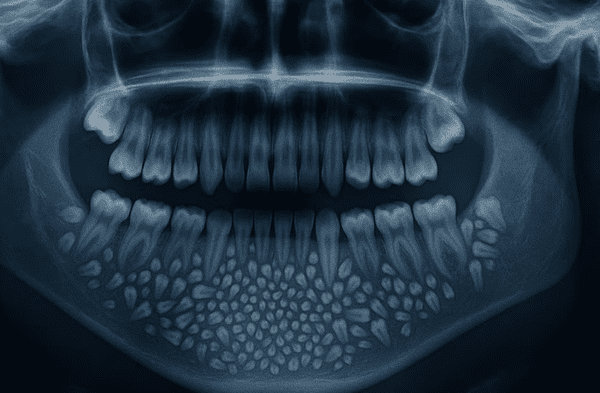

Un caso médico excepcional quedó registrado en la historia de la odontología en 2019, cuando especialistas del Hospital Universitario de Saveetha, en Chennai (India), lograron extraer 526 dientes de la mandíbula de un niño de siete años. La cirugía, que se extendió por una hora y media, permitió descubrir una extraña anomalía que había permanecido oculta durante años dentro de una masa tumoral benigna.

Los estudios radiográficos y las tomografías mostraron una masa de cerca de 200 gramos en el interior de la mandíbula. El Dr. Senthilnathan, jefe del Departamento de Cirugía Oral y Maxilofacial, determinó que se trataba de un “odontoma compuesto”, un tipo de tumor benigno relacionado directamente con la formación dental.

“La especie de tumor que detectamos impidió el crecimiento permanente de los molares en el niño en el lado afectado”, explicó el cirujano tras la intervención. Los exámenes médicos evidenciaron múltiples dientes rudimentarios agrupados en un saco, una presentación poco común en la literatura científica.

El resultado sorprendió incluso a los profesionales con mayor experiencia. De acuerdo con Science Alert, el saco contenía 526 piezas dentales en miniatura que variaban entre 0,1 milímetros y 15 milímetros de longitud. El proceso de clasificación y conteo de cada diente tomó cinco horas adicionales de trabajo de laboratorio.

La Dra. Pratibha Ramani, directora del área de Patología Oral y Maxilofacial, resaltó que todas las piezas extraídas poseían las características propias de un diente normal: corona, raíz y esmalte. “Incluso la pieza más pequeña tenía las características de un diente tradicional”, precisó la especialista, remarcando que no existen antecedentes con tal cantidad de dientes en registros médicos internacionales.